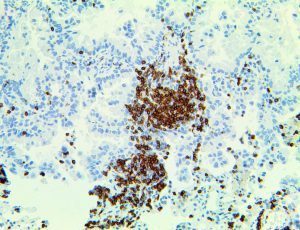

It is the ICU physician who is most likely to witness one of the deadliest manifestations of the abnormal immunological response, the cytokine storm syndrome (CSS). This response is also referred to by some as the cytokine release syndrome (CRS). CSS is characterized by continuous activation and expansion of macrophage and lymphocyte populations, which secrete large amounts of cytokines, causing the cytokine storm. This massive cytokine release is akin to hemophagocytic lymphohistiocytosis (HLH) disease, a syndrome characterized by initial unchecked and persistent activation of cytotoxic T lymphocytes and NK cells.

Clinical and laboratory manifestations of HLH include fever, enlarged liver and/or spleen, neurologic dysfunction, coagulopathy, liver dysfunction, cytopenias (i.e., low levels of erythrocytes, leukocytes, and/or platelets), hypertriglyceridemia, hyperferritinemia, hemophagocytosis, and eventually diminished NK cell activity as the immune system becomes progressively paralyzed. HLH can be familial (primary HLH) or secondary to another disease process (sHLH), such as rheumatic disease, in which it is referred to as macrophage activation syndrome (MAS, characterized by elevated ferritin).